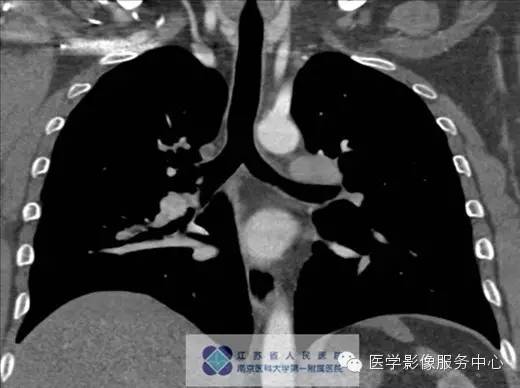

影像分析:右侧肺门处见小团块状密度增高影,密度尚均匀,边缘毛糙,增强扫描病灶不均匀强化。

病理:肺神经内分泌瘤